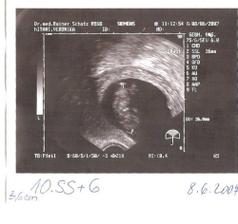

Narodila sa 29.12.2007 o 23.02 hod v klinike sv. Hedvigi v Regensburgu (Nemecko) s nadhernymi mierami: 50cm, 3280g a obvod hlavicky 33,5cm....